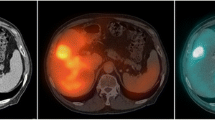

Marrow cavities in spine, pelvis and femur were identified on CT. In order to delineate bone marrow on SPECT slices, regions of interest (ROIs) were drawn on CT slices identifying the marrow tissue. Preserving geometry, the marrow ROIs were then transferred onto corresponding SPECT slices of SPECT/CT scan, allowing uptake quantitation (Figs. 1, 2). The marrow ROIs were divided into three volume of interest (VOI) compartments: spinal marrow, pelvic marrow and femoral marrow. Average counts in each marrow VOI were then converted to activity and activity concentration using calibration factors (see Appendix 1 for a detailed description of calibration of the SPECT/CT scanner). Activity concentration in the bone marrow was then estimated based on activity in the marrow VOIs by correcting for yellow marrow and bone tissue volumes. The correcting factor for yellow marrow volume R was based on ICRP 70 marrow cellularity values and the correcting factor q for bone tissue was based on measurement of CT intensities in marrow VOI (see Appendix 2 for a detailed description of the method).

If haemopoietically active marrow contains CD20-positive cells, uptake in active marrow will be elevated (Fig. 1). This will lead to a radiation absorbed dose deposited in the active marrow which cannot be accounted for by any method currently used in clinical practice. Macey et al. [9] proposed the use of planar imaging of the lumbar spine for quantification. In our extended protocol, we incorporated lumbar spine planar imaging, although it became apparent that this technique was not reliable in our patients. Our SPECT/CT imaging data showed clearly that the majority of NHL patients have para-aortic node involvement (Fig. 2), in which uptake is quite intense, although it may not be demonstrable on planar images. Furthermore even after 5 days there is relatively high activity in major blood vessels (Fig. 2), especially in the aorta, which will be in the field of interest on planar lumbar spine images. Counts from involved lymph nodes and aortic activity cannot be easily differentiated from counts from marrow (Figs.1, 2). Thus planar imaging techniques are unlikely to be reliable for accurate bone marrow uptake quantitation for 131I-rituximab in NHL patients.